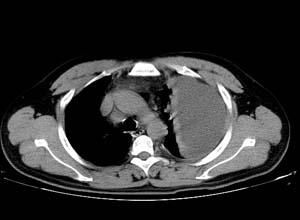

肋間神經炎、帶狀皰疹、食道炎均可引起胸痛,帶狀皰疹時劇烈胸痛,沿肋間走行,1~2天后皮膚出現密集性疼痛,也有可能是肺大泡、小量氣胸,建議進一步做CT或磁共振檢查。